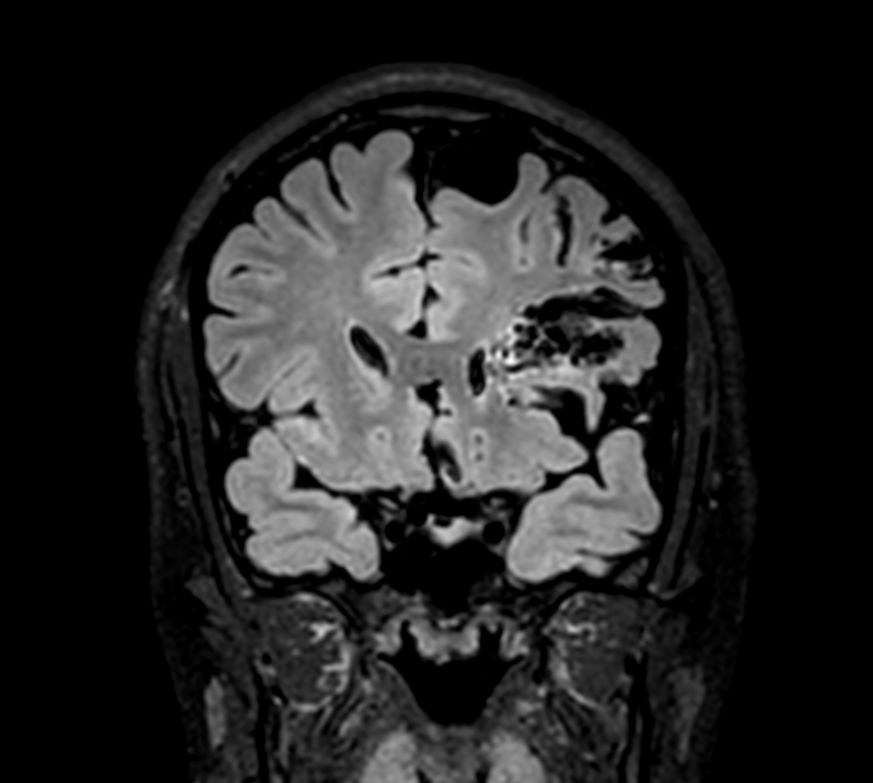

3D T2w FLAIR - Coronal reformatCompressed SENSE

-